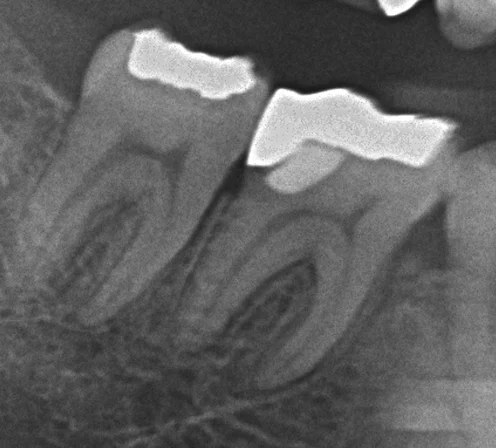

歯肉縁下深くに及んだ二次う蝕をダイレクトボンディングで修復

群馬県からお越しの男性歯科医師の患者さんです。右下7番 遠心の歯肉縁下深くに及ぶ二次う蝕を、ラバーダム防湿下でダイレクトボンディング修復しました。遠心エナメル質はクラックに沿って崩れたもので、感染歯質はエナメル象牙境付近に限局。良好な隔離環境を確保でき、適合の良い仕上がりが得られた症例です。